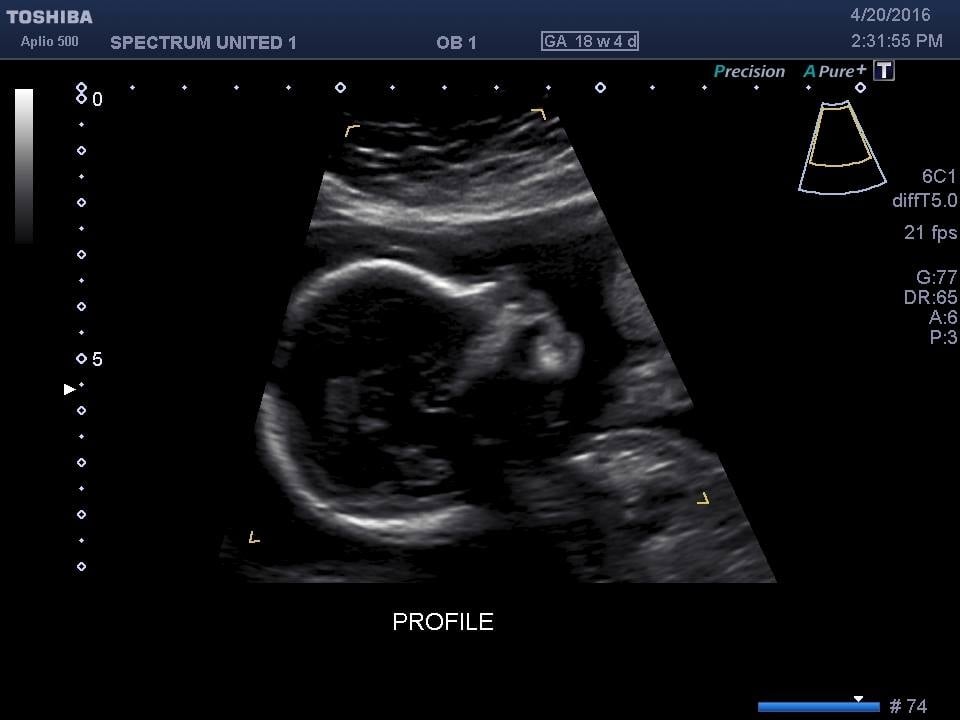

Baby H at my 18w U/S yesterday... After over an hour of looking and measuring and not being able to see the sex due to LO keeping the legs crossed, I was told to empty my bladder and we would try again. LO not only uncrossed it's legs, but completely flipped over... It's a Girl!